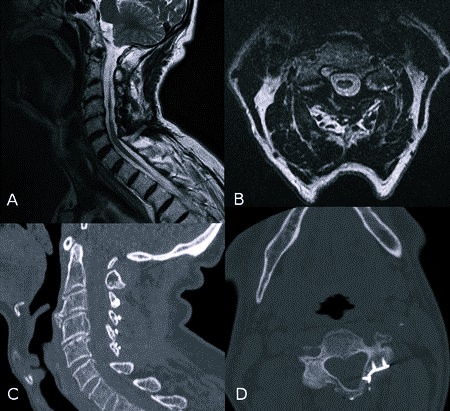

- рентгенография шейного отдела позвоночника, позволяющая выявить травматические и нетравматические нарушения в опорно-двигательном аппарате. На рентгенограмме специалист может выявить переломы позвонков, деформацию межпозвонковых дисков, остеофиты и др. Метод используют на начальных этапах диагностики для определения характера патологии и выбора дальнейшей тактики обследования;

- компьютерная томография — вариант рентгенографического исследования, позволяющий получить объемное изображение позвоночника и расположенных рядом тканей. Используется для выявления признаков поражения костно-суставного аппарата;

- магнитно-резонансная томография подходит для оценки состояния межпозвонковых дисков, нервных корешков, сосудов и мягких тканей. Указанные образования плохо видны при рентгенологическом исследовании. С помощью МРТ выявляют опухоли, воспалительные процессы в нервной системе и т.п.;